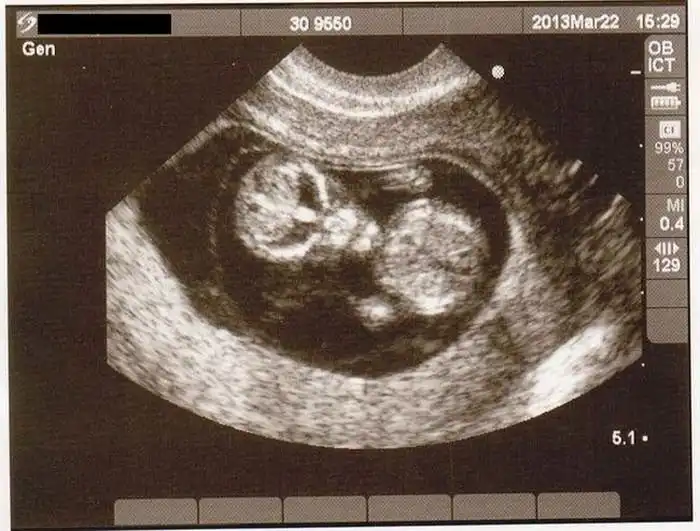

На экранах аппаратов УЗИ дети, находящиеся в утробе матери, выглядят далеко не такими милыми и симпатичными, какими они оказываются после своего рождения.